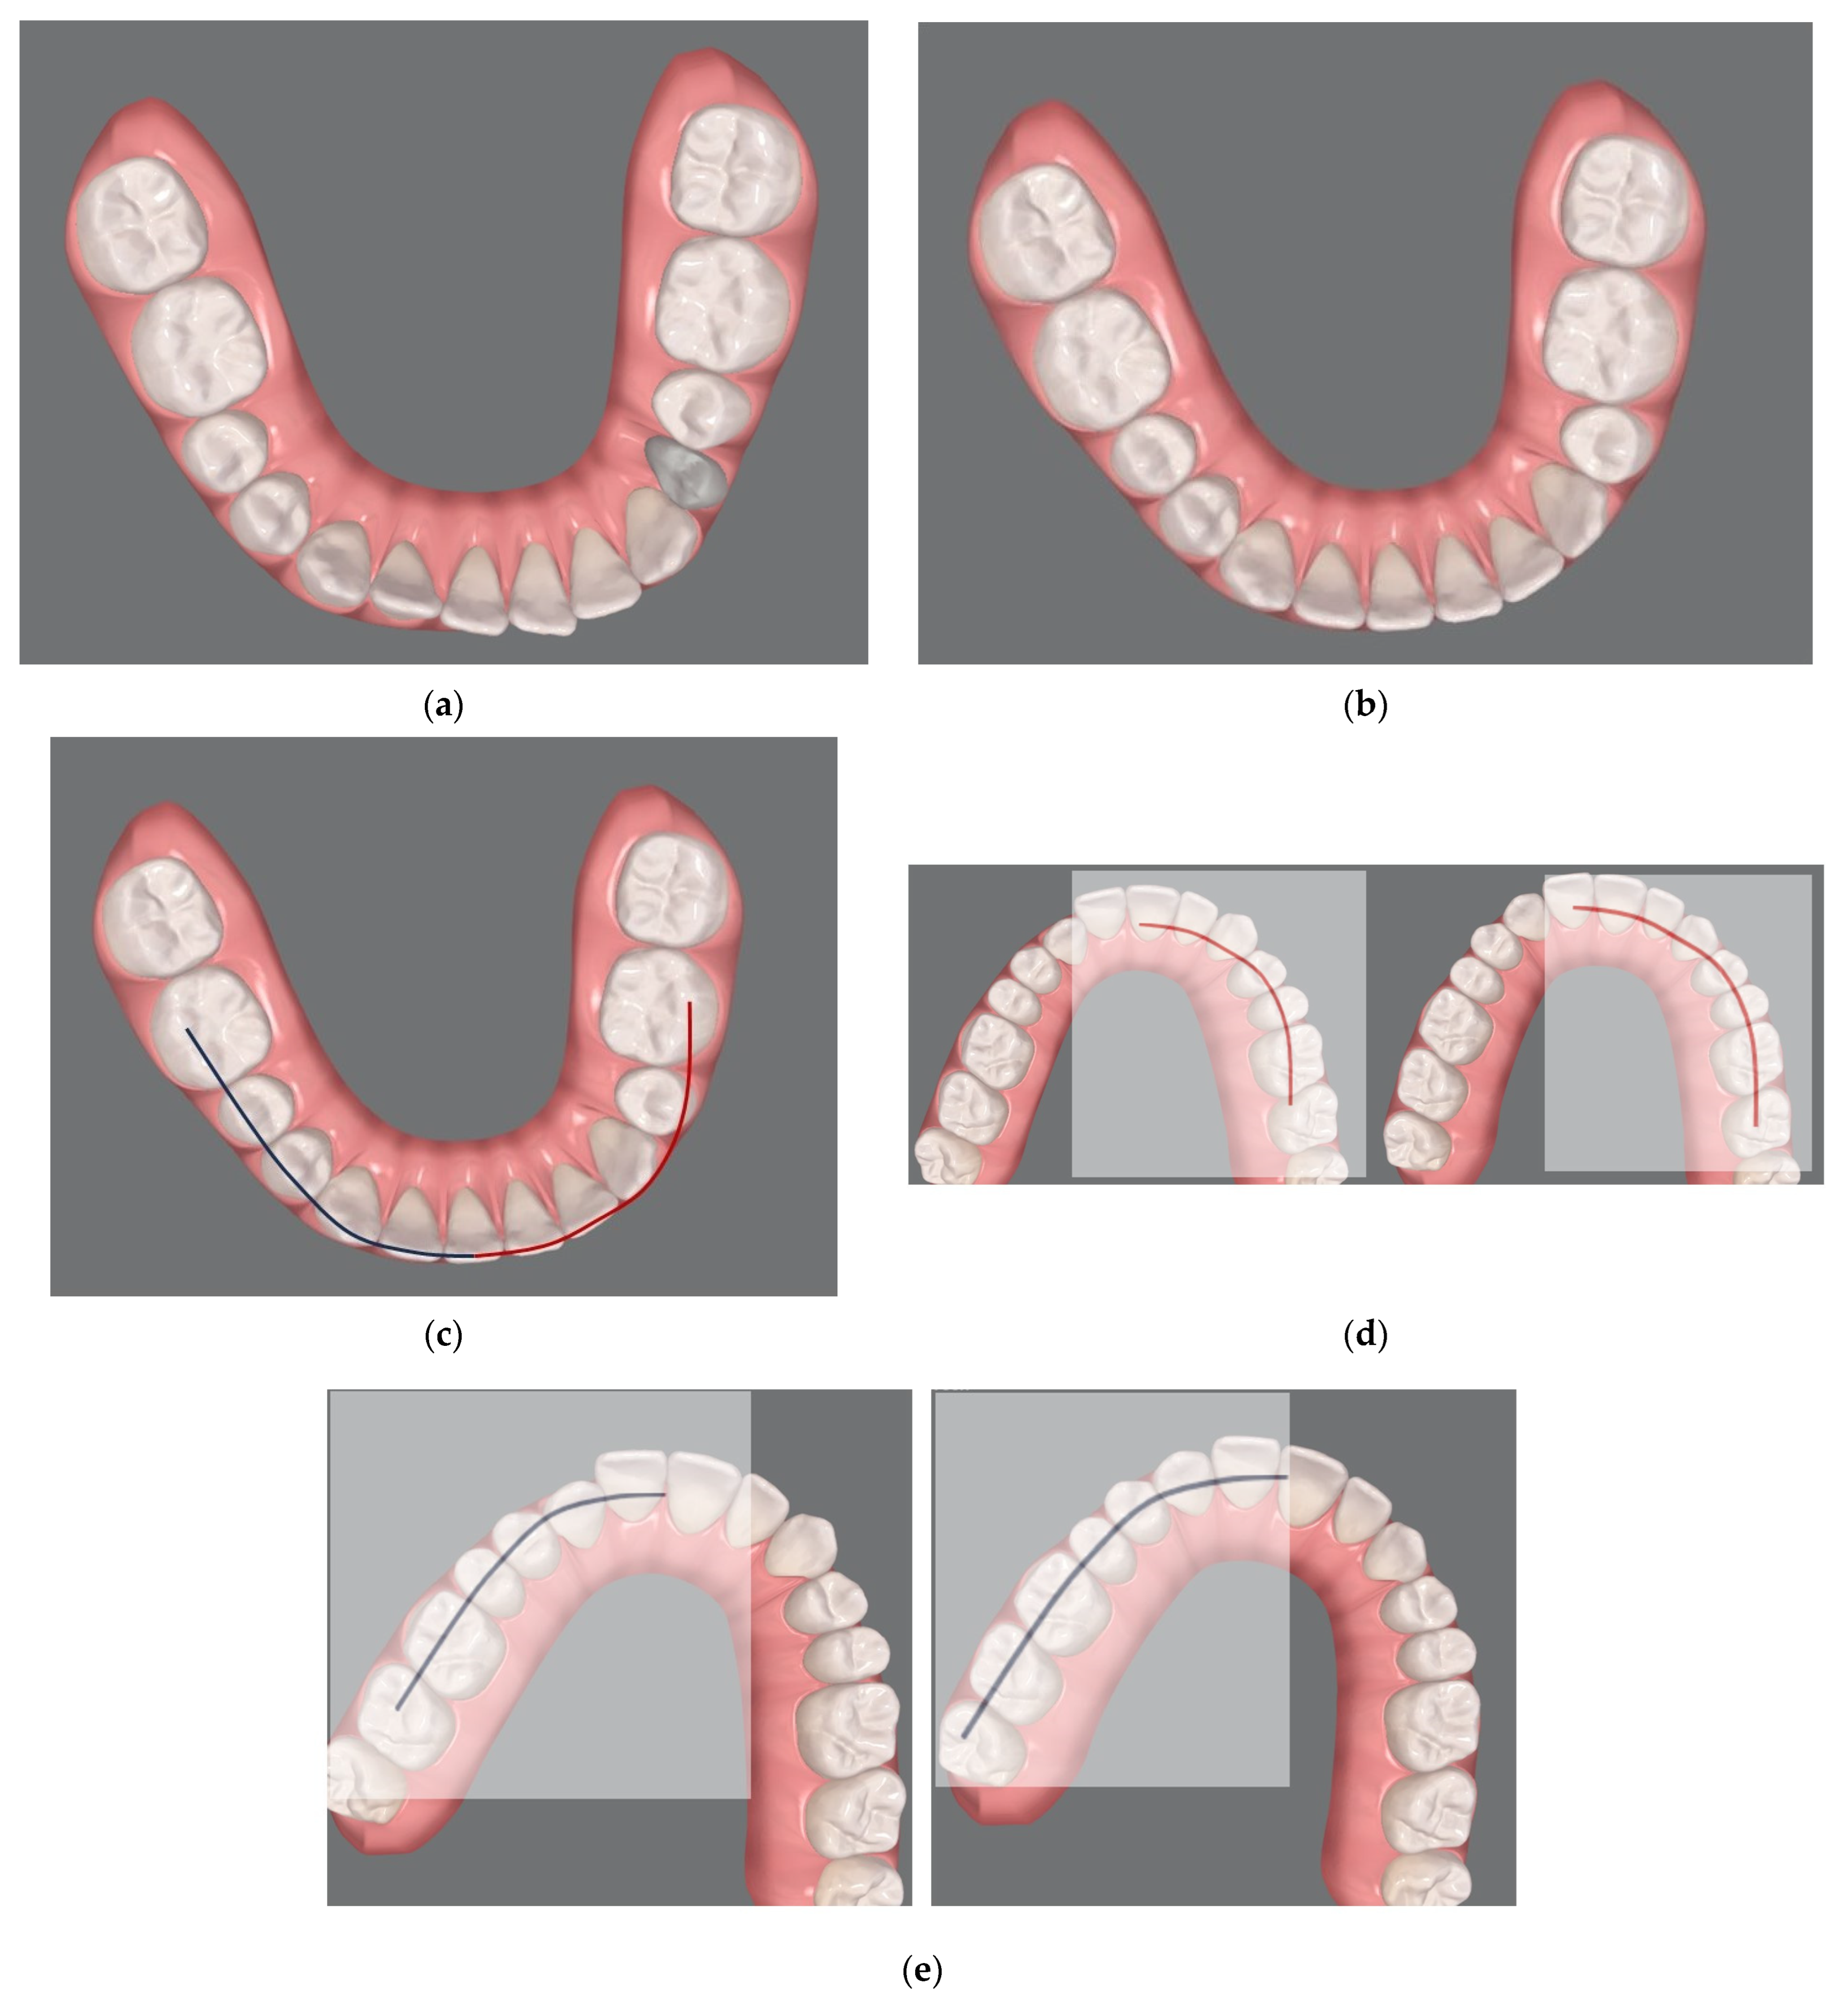

Pre-Surgical Orthodontic Treatment

- Clear aligner technique